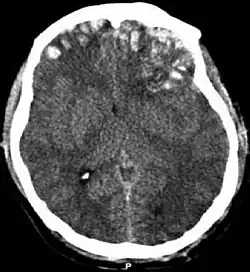

Traumatisk hjerneskade (TBI), også kendt som intrakranial skade, opstår når en ydre kraft skader hjernen. TBI kan klassificeres baseret på sværhedsgrad, mekanisme (lukket eller åben hovedlæsion) eller andre træk (eksempelvis opstået på en specifik lokation eller over et bredere område). Hovedskade er en bredere kategori der involverer skader af andre strukturer såsom issen og kraniet. TBI kan resultere i fysiske, kognitive, sociale, emotionelle og adfærdsmæssige symptomer, og det kan ende med alt fra fuldstændig helbredelse til permanent funktionsnedsættelse eller død.